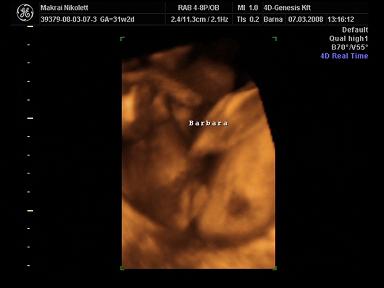

2008.03.07 19:39